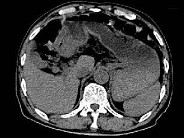

- 单项选择题根据所提供的图像,最可能的诊断是 ( )

A、胃淋巴瘤

B、胃平滑肌瘤

C、胃窦癌

D、胃窦炎

E、以上都不是